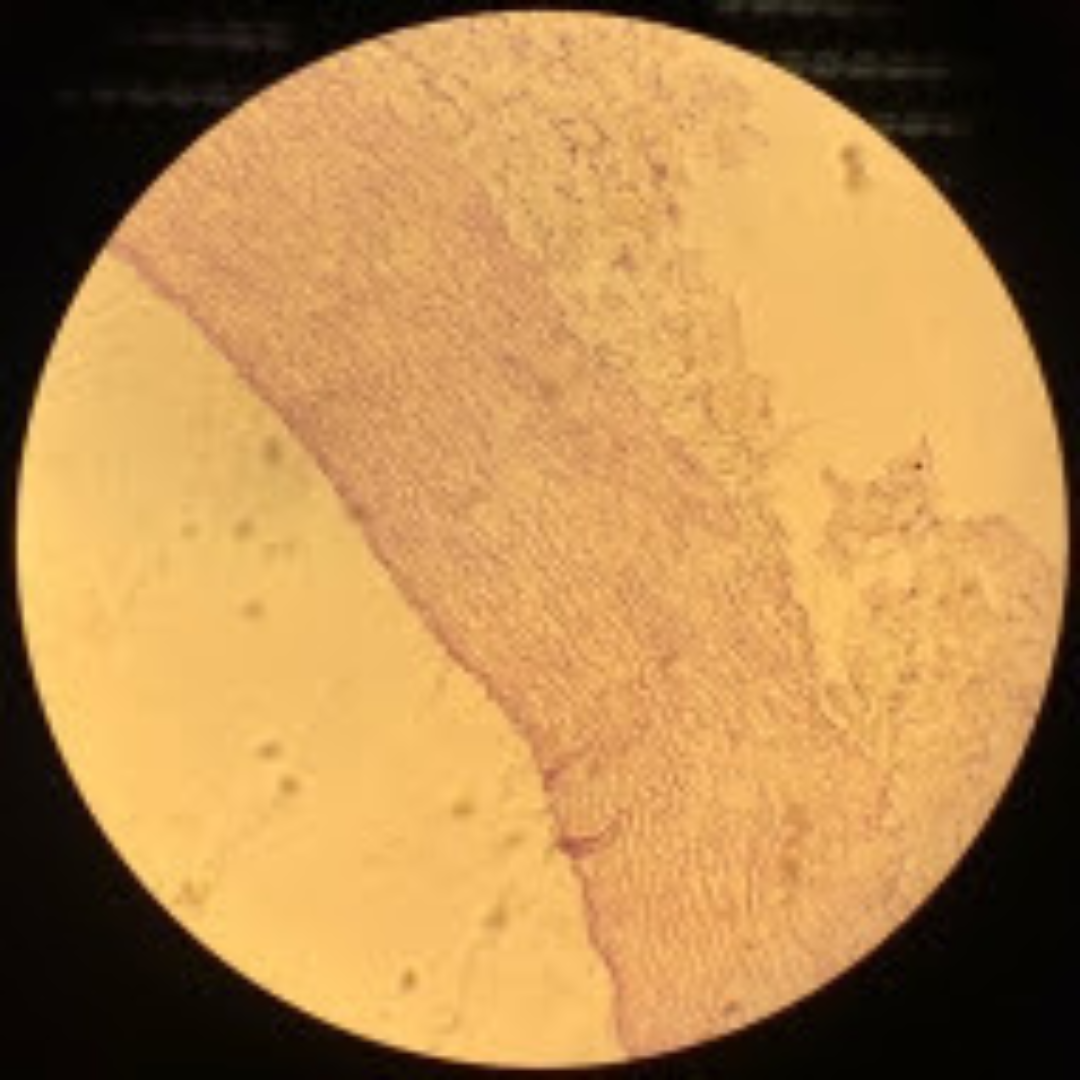

Dense Regular Collagenous Connective Tissue (Fibrous Tissue)

Dense Regular Elastic Connective Tissue (Elastic Tissue)